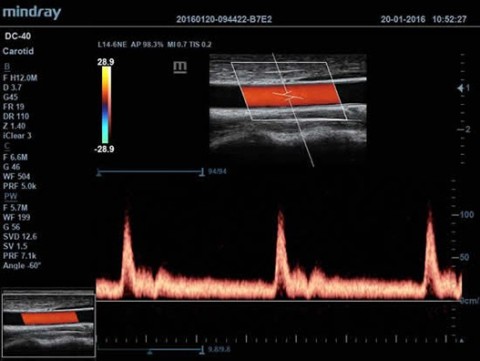

- Режимы сканирования B/M/Цветовой доплер CDI/Цветной M/Энергетический доплер PD/Направленный энергетический доплер Dir.PD

- Импульсно-волновой доплер (включая режим высокой частоты повторения импульсов HPRF)

- Auto IMT Package (automatic measurement for Intima-Media Thickness) - Автоматический расчет толщины комплекса интима-медиа

- DICOM DICOM Vascular S/R - Структурированный отчет по ангиологии в формате DICOM DICOM Cardiac S/R - Структурированный отчет по кардиологии в формате DICOM

Доплер:

Да